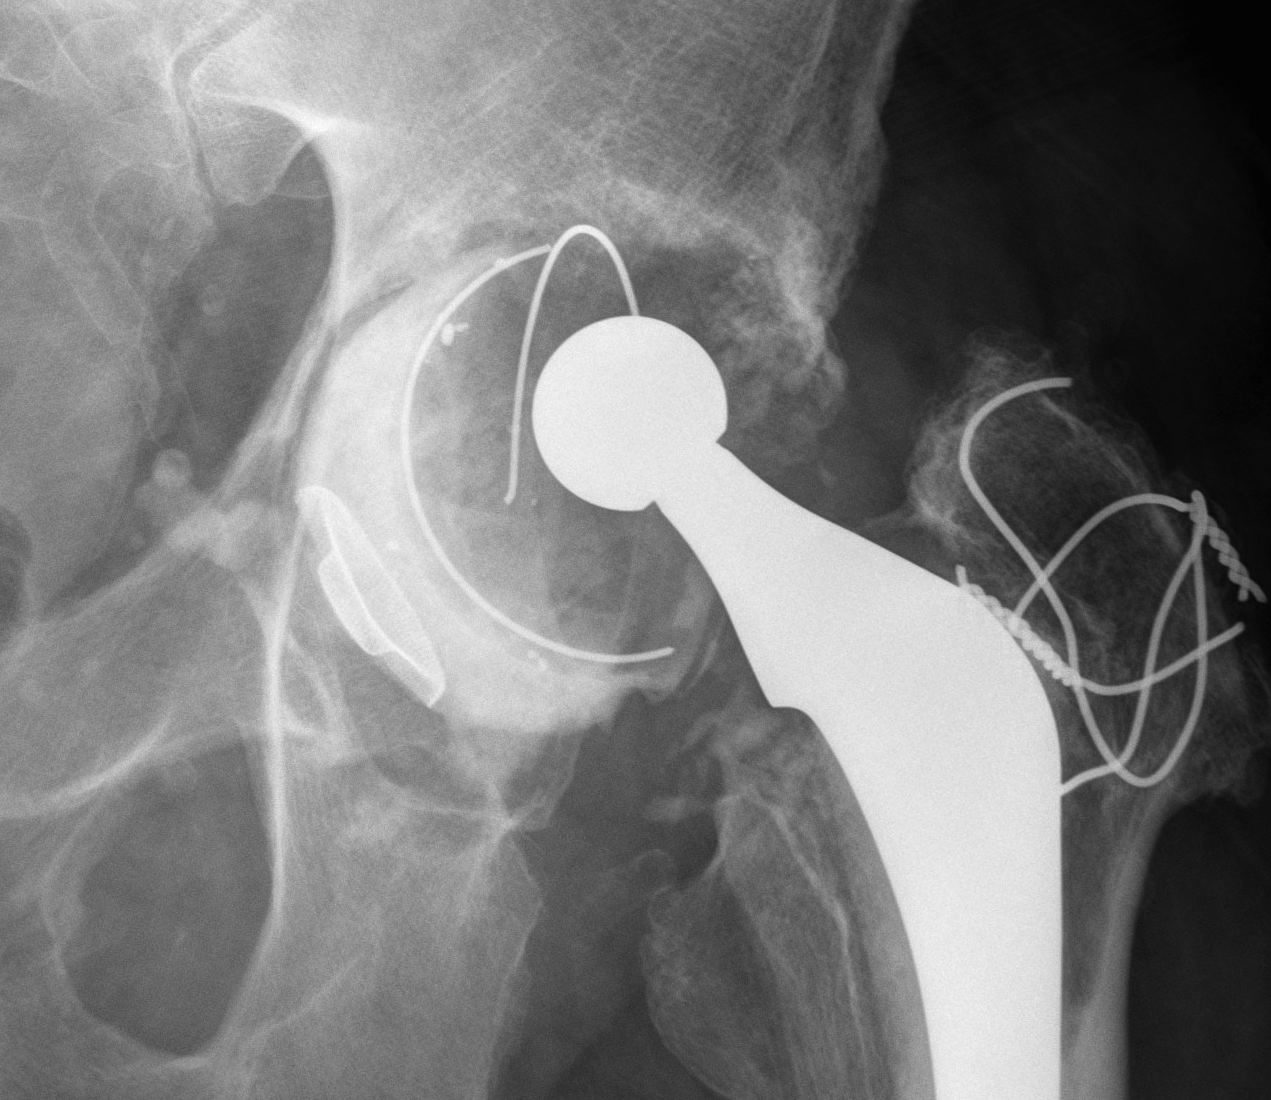

A. Allograft + Antiprotrusio Cages + Cemented Cup

Types

- Ganz / Muller / Burch Schneider

- variations on them

- hook or screws into ilium

- hook or screws onto ischium

- can have extension for screws onto pubis